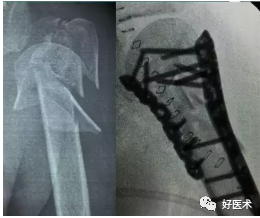

2.锁定板固定:

-

适用肱骨近端粉碎性骨折

不容易出现螺钉松动、退钉等情况,碎骨片固定后不容易发生二次移位

更适用于老年骨质疏松的患者

可以进行早期安全的功能锻炼

3.钢板螺钉内固定

对于骨质疏松的老年人三部分骨折,选用AO的LCP系统锁定钢板。